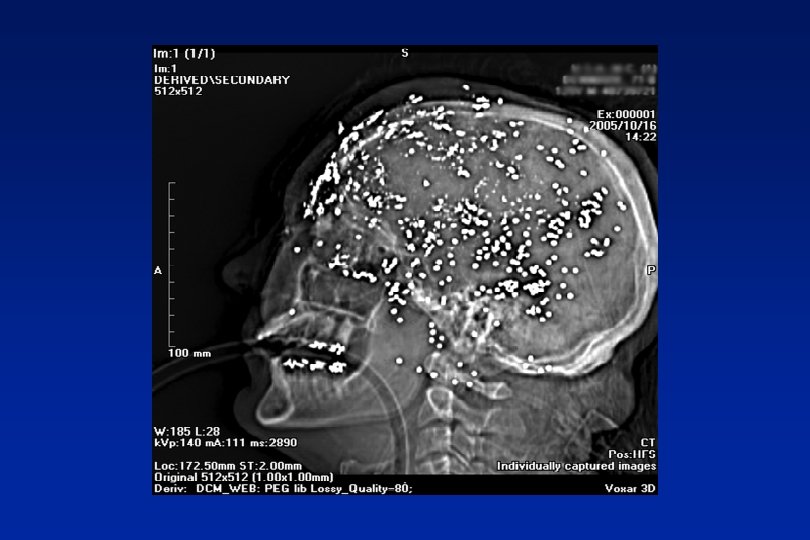

Primary Tumours n Meningioma 20% - 10 yr survival 80% n Glioma 70% - 5 yr survival 20% n Misc. 10% - Variable

Headache and tumour n Headache prevalence with tumour 70%+ n Headache at presentation 50% n Headache alone at presentation 10% (Iverson 1987)

Risk of brain tumour with headache presenting to primary care (Kernick 2008) Risk % Undifferentiated headache Primary headache Under 50 0. 09% 0. 03% Over 50 0. 28% 0. 09%

We need to scan when the advantages out way the disadvantages Reassurance, Diagnosis/treatment Cost, exposure incidental pathology (4 -10%)

Luftwaffe pilots (n-2370) Weber 2006 n 93% normal (25% variations of norm) n 6. 7% abnormalities n 56 cysts; 13 vascular abnormalities; 4 adenomas; 4 tumours

Red Flags Probability of significant morbidity or mortality >1%. Need urgent investigation n Abnormal neurological symptoms or signs n New seizure n History of cancer elsewhere

Orange Flags Headache presentations where probability is likely to be 0. 1% and 1%. Need careful monitoring and low threshold for imaging n Aggregated by Valsalva manoeuvre n Headache with significant change in character n Awakes from sleep n New headache over 50 years n Memory loss n Personality change